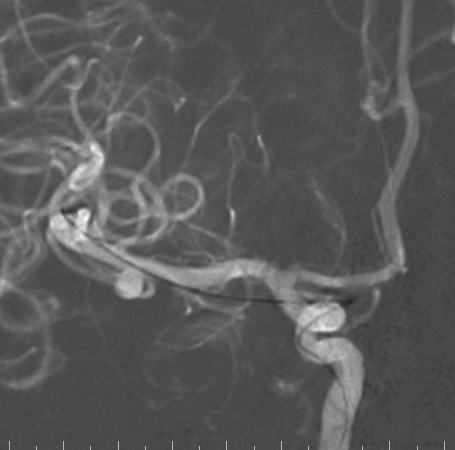

右侧颈总造影:右侧大脑中动脉瘤

右侧大脑中动脉瘤,瘤颈处发出颞支,颈宽3.79mm,瘤高3.51mm,远近端载瘤动脉直径分别为2.43mm、2.52mm。